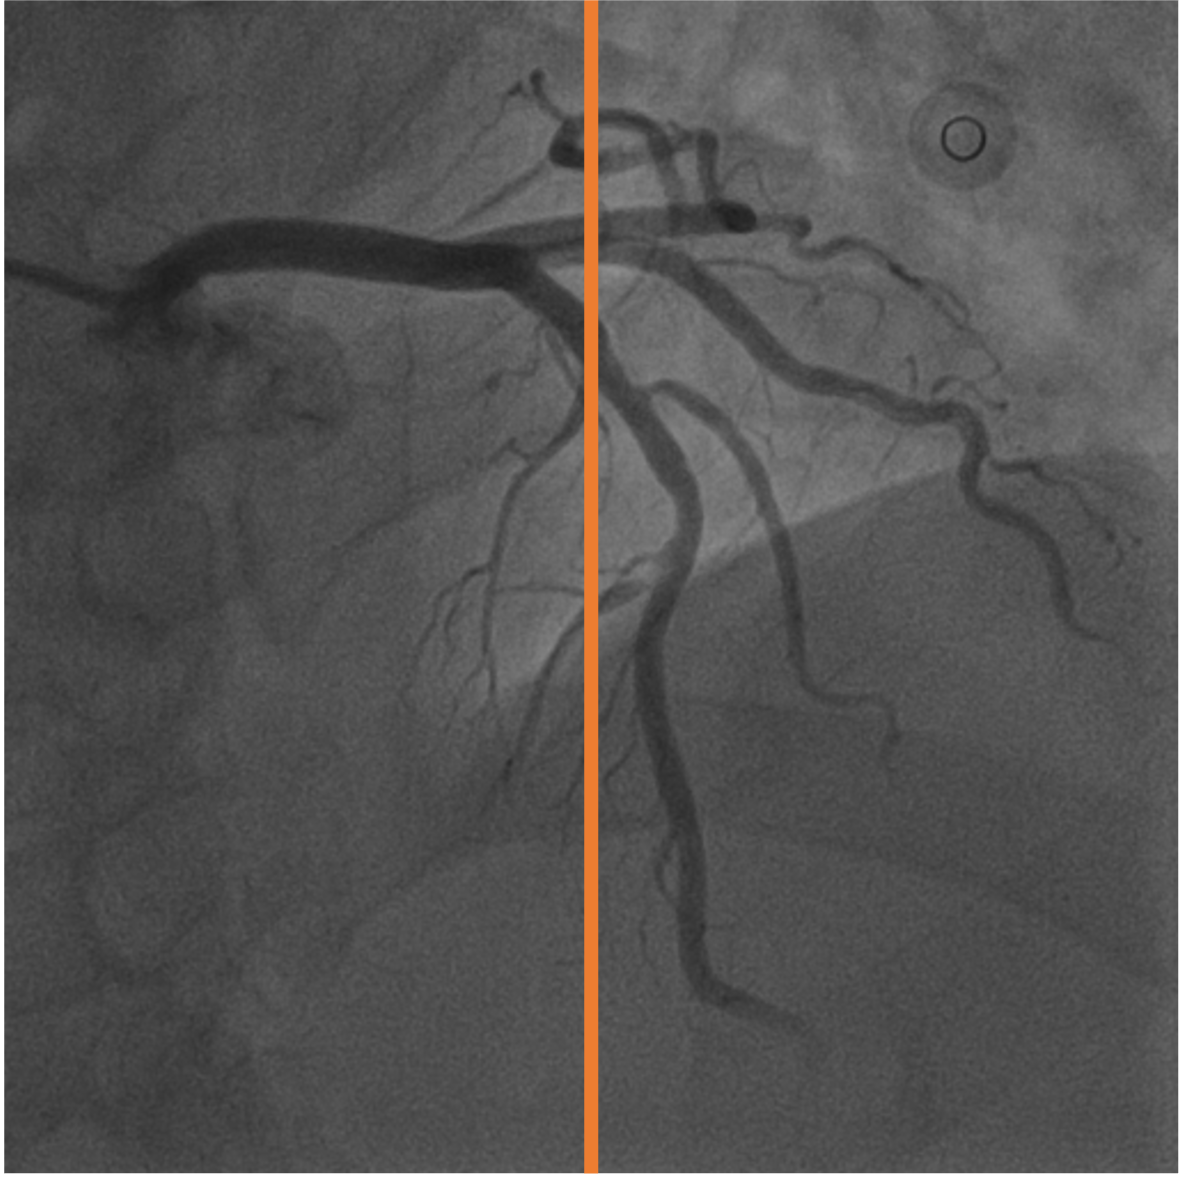

7 Temporal Coherency

Our method takes an entire X-ray video as input, thus producing segmentation results with better temporal coherency. Temporal coherency is essential for making medical diagnoses, especially when dealing with blood flow in vessels. Therefore, we conduct visual comparisons between our method and other compared methods by slicing horizontally or vertically and stacking the segmentation results. The results in Fig. 14 show our method strikes a better balance between segmentation accuracy and temporal coherency. While other baseline methods either produce false segmentation results or do not maintain consistent prediction along the temporal dimension.